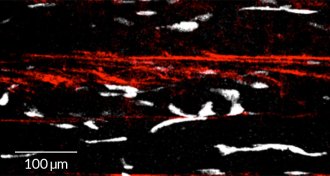

Muscle repair gets spooky help

Ghost fibers are tunnels that stem cells can use to rebuild muscles fiber by fiber.

By